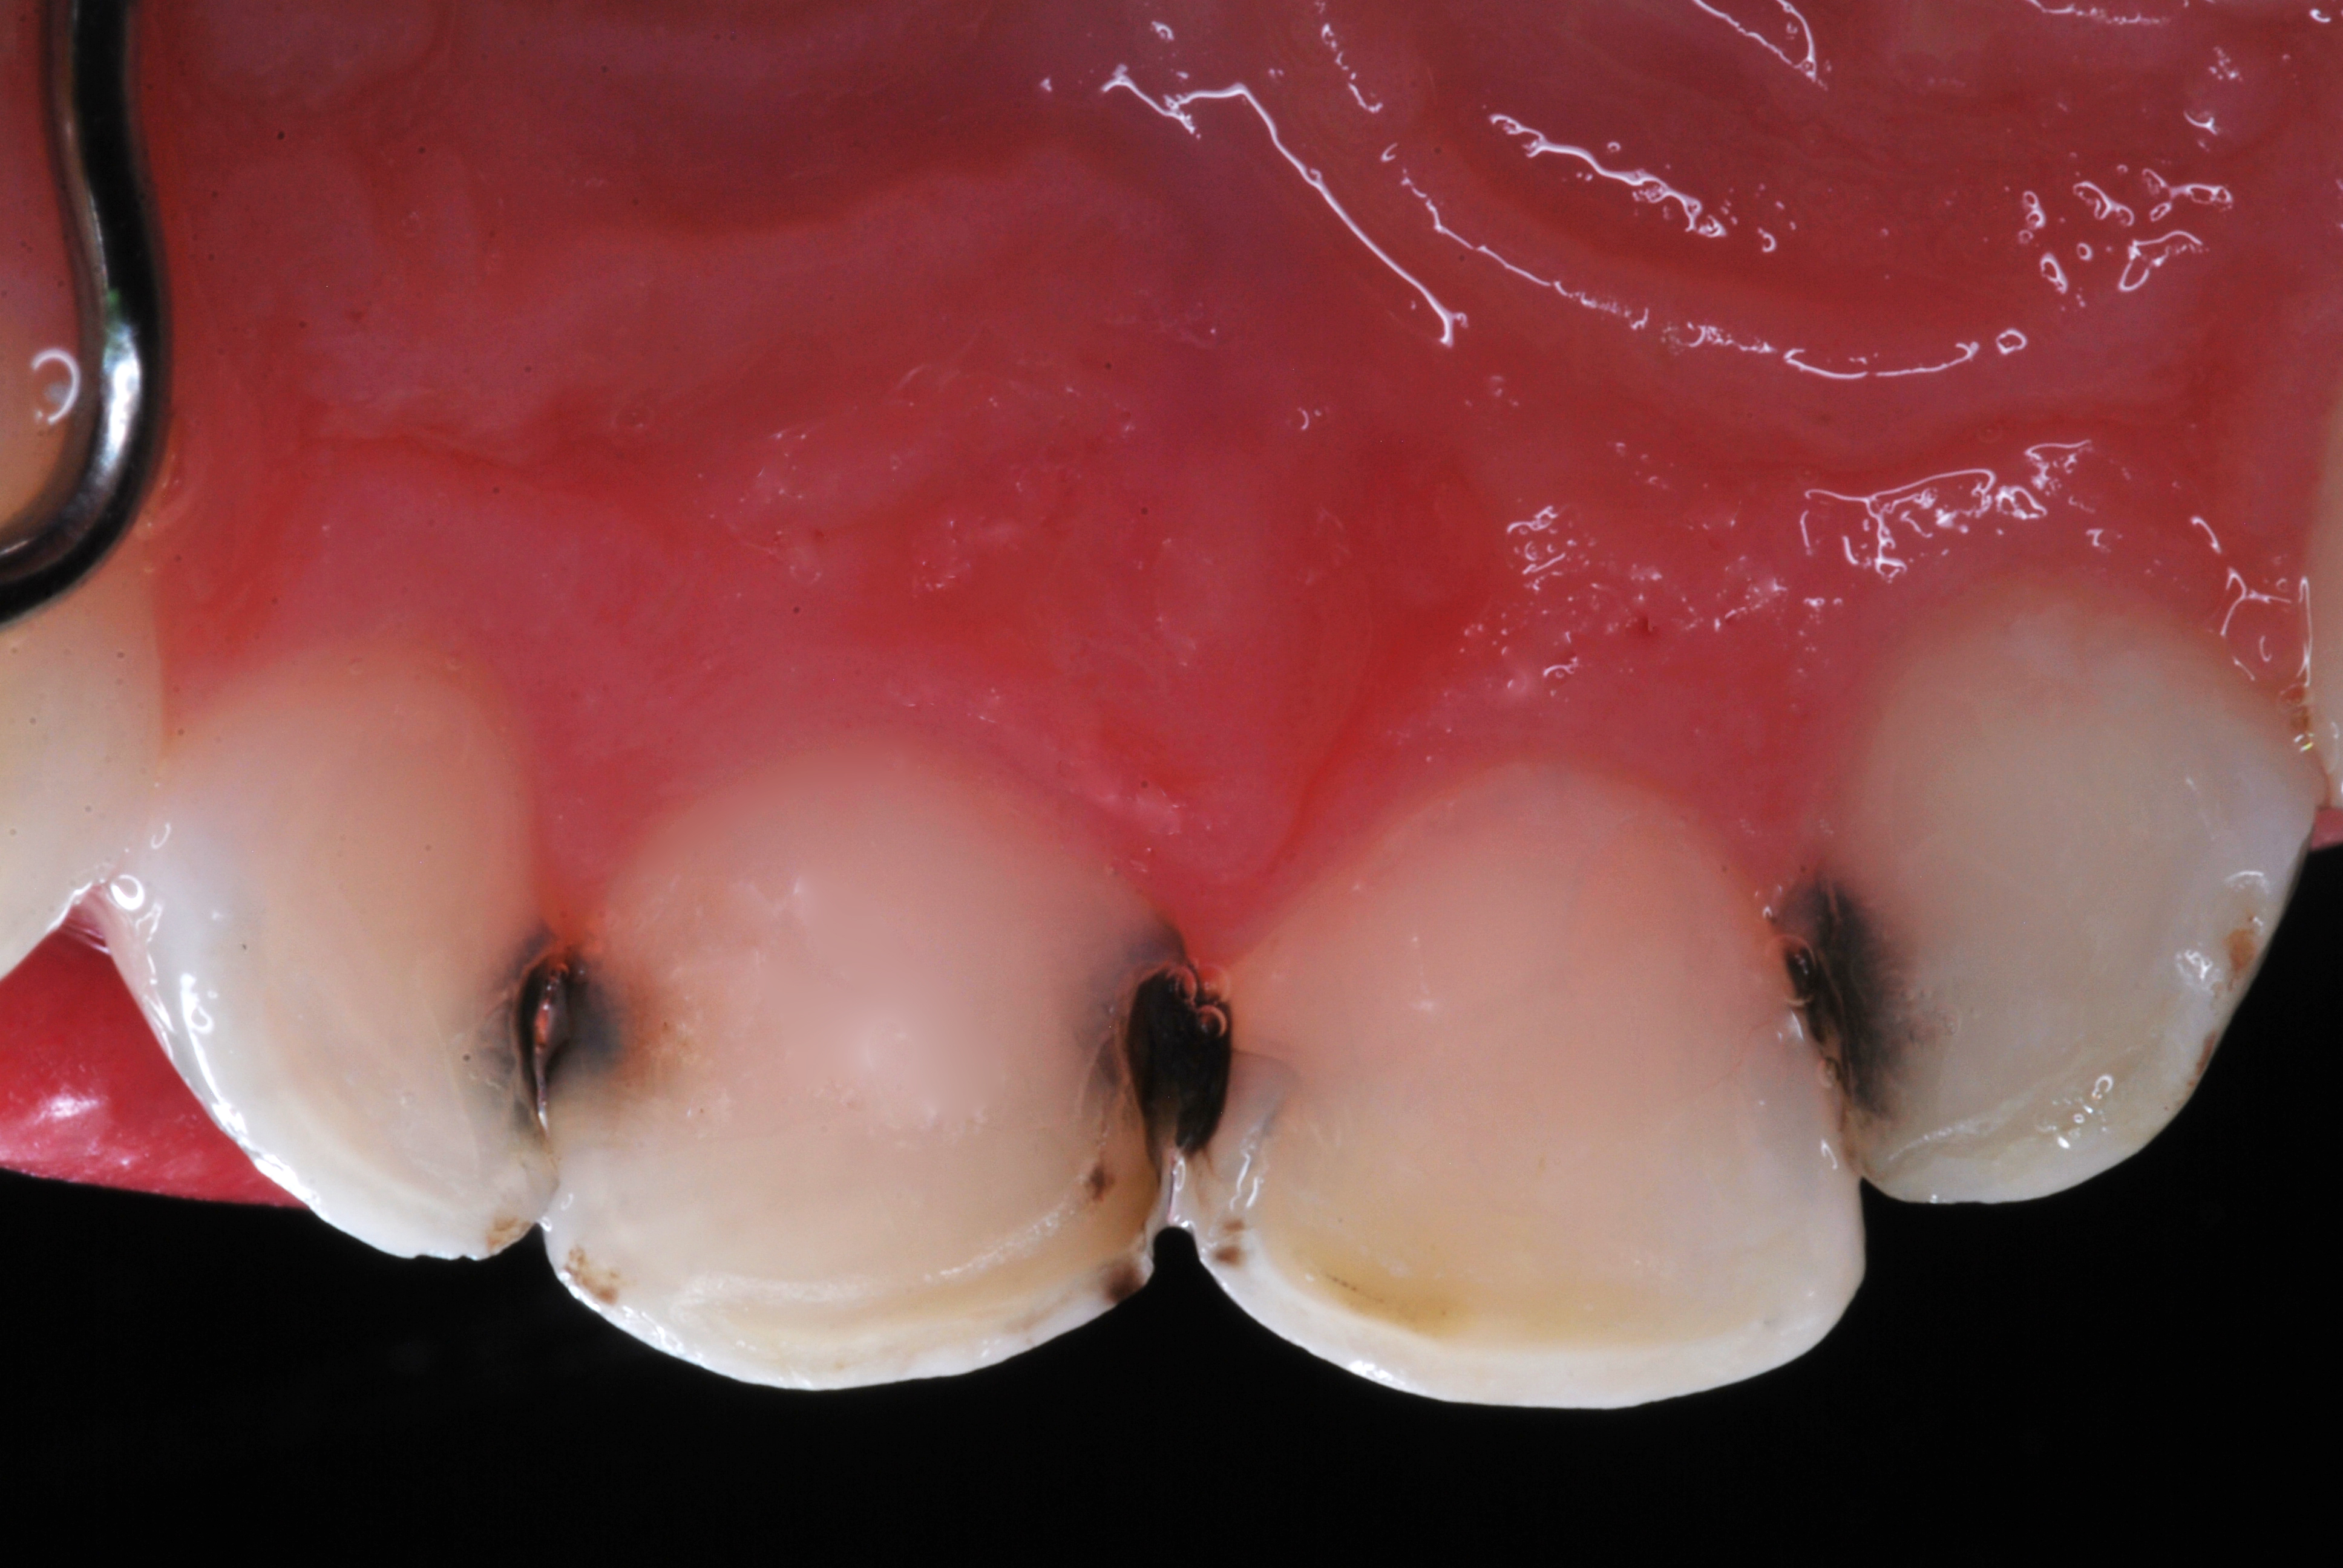

(6.) After exposure of disto-occlusal caries, SDF is applied, followed by a coating of fluoride varnish.

Figure 6

(7.) After exposure of disto-occlusal caries, SDF is applied, followed by a coating of fluoride varnish.

Figure 7

(8.) After exposure of disto-occlusal caries, SDF is applied, followed by a coating of fluoride varnish.

Figure 8